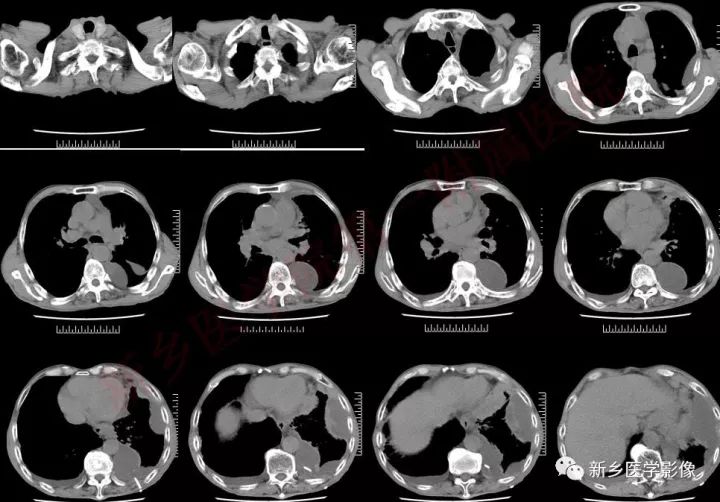

肿块形态及强化:

中央型小细胞肺癌主要起源于5级以上支气管,分叶少,边界较光滑,不易发生空洞,肿块一般沿支气管长轴蔓延,包绕支气管,增强后呈中度强化;周围型小细胞肺癌,肿块多呈结节状或葡萄状,结节状病灶多为单结节型,形态较规整,边缘较光滑,无分叶或浅分叶,毛刺征及胸膜凹陷出现率低;葡萄状病灶表现为沿小支气管生长的串珠状大小不等结节病灶,密度较均匀,少有空泡征、空气支气管征,增强后,出现轻中度强化。这主要与小细胞肺癌的病理形态有关,小细胞肺癌,癌细胞小而呈短梭形,胞浆少,癌细胞排列密集,因此形成的肿块密度较大,瘤体密实,内聚力强,纤维成分少,血供相对丰富,肿块各方向生长的速度也较均衡,使得小细胞肺癌肿块不容易形成较深的分叶和空洞。

淋巴结与淋巴管

病理上小细胞肺癌纤维成分少,肿块密实,血供相对丰富,肿块周围淋巴结、淋巴管受侵犯。反映在CT表现为自肿块向周围肺野放射状排列的线状阴影、间隔线、颗粒状阴影及胸腔积液。美国退伍军人医院肺癌研究组分期系统把小细胞肺癌分为局限期和广泛期的依据之一,就是对侧肺门和锁骨上淋巴结肿大即为广泛期。可见淋巴组织的受侵对于小细胞肺癌的治疗和预后具有重要意义

血管:

小细胞肺癌的沿支气管壁生长的特点,加上其肿块周围的淋巴结、淋巴管弥漫受侵的特性,使得小细胞肺癌周围肺间质广泛受侵,间质增厚,其中的血管壁受侵甚至管腔内受侵有癌栓形成,造成受侵血管呈“冰冻状”。中央型小细胞肺癌,肿块较大时肿块与肺门、纵膈的肿大淋巴结融合,包绕临近较大血管形成“冰冻纵膈”。CT表现为肺动脉主干或分支最常见。

胸腔积液与胸膜

小细胞肺癌沿淋巴管扩散的特点,容易造成小叶间隔线增厚、凸起,当侵及胸膜时,可引起胸膜多发结节影或磨玻璃影,伴有恶性胸腔积液。CT表现为胸膜面不规则增厚、凹凸不整的细小结节影及胸腔积液,增强可见增厚的胸膜及结节影轻至中度强化表现。按照美国退伍军人医院肺癌研究组分期系统标准,双侧胸腔积液发生时,病情已进展到广泛期,对于患者的治疗和预后将产生重要的影响